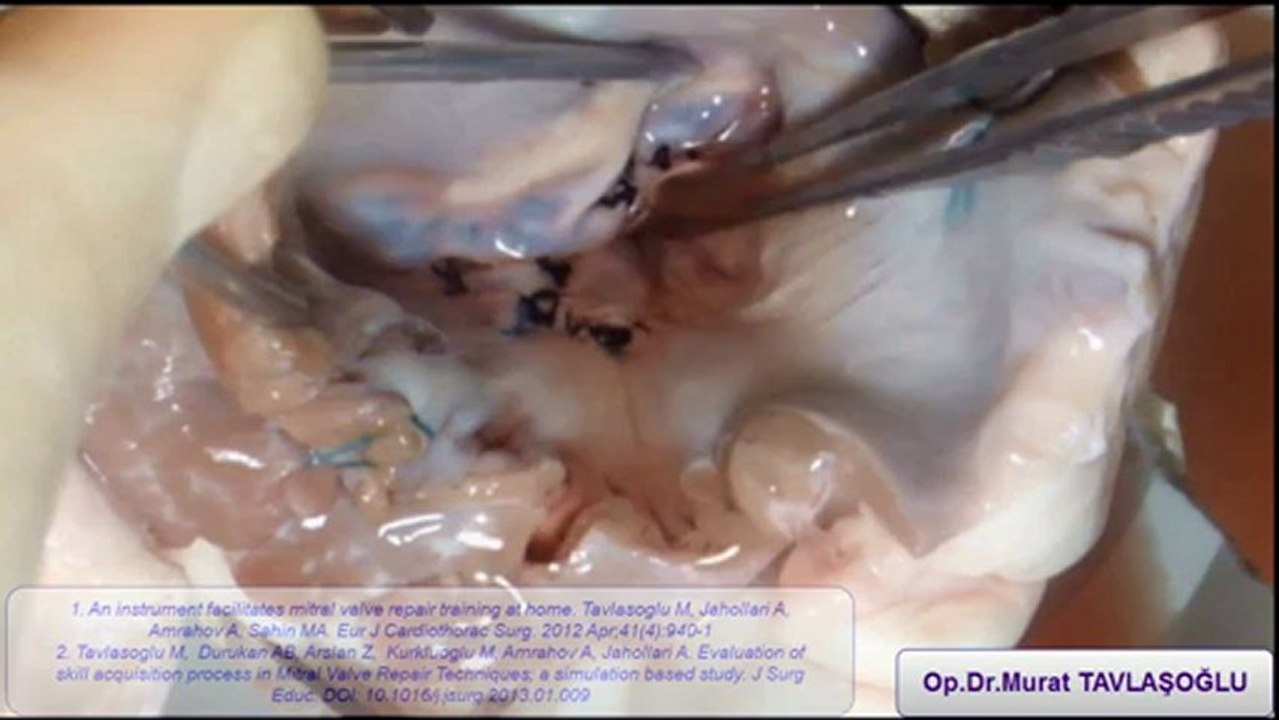

Posterior-anterior chorda nakli- posterior quadranguler rezeksiyon-anteriortrianguler rezeksiyon 5:04

Posterior-anterior chorda nakli- posterior quadranguler...

mtavlasm 1 views

Kardiyovaskuler Cerrahi 20 views